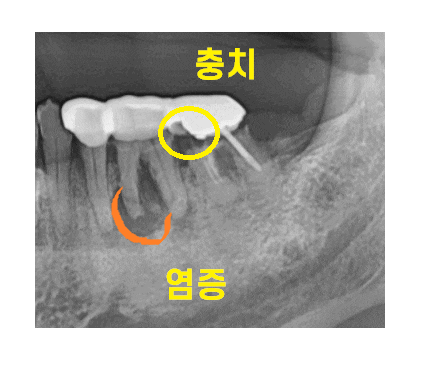

오래전 하신 은니가 문제였는데요.

23.05.22

오래 쓰셨습니다.